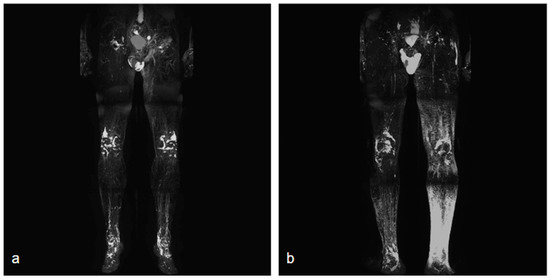

None of the procedures mentioned above could restore the non-functional lymph vessels along the entire length of the limb. To address this challenge, some groups have begun incorporating nanofibrillar collagen scaffolds (BioBridge™, Fibralign Corp., Union City, CA, USA) to improve surgical strategies in patients with advanced lymphedema. Nanofibrillar collagen scaffolds mimic the collagen matrix that supports lymphatic vessels and can significantly promote lymphangiogenesis. Some preclinical and initial clinical studies suggest that the use of collagen scaffolds in routine surgery improves the outcome of microsurgical procedures in patients with lymphedema, showing promising results both in association with vascularized lymph node transplantation and LVA. Their capillary action aids the initiation of interstitial flow and appears to serve as a scaffold for endothelial cell attachment and alignment, leading to the restoration of small lymphatic ducts [67,82,83] (Figure 4).

Figure 4. Two intraoperative images showing the use of Biobridge™ in a patient with secondary lymphedema.